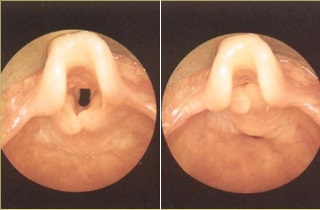

Если сравнить рассеченное фото хрящевого клапана в состоянии нормы с аналогом в состоянии воспаления, то на снимке будет четко виден этот дефект.

При исследовании строения надгортанника у взрослых и детей на фотографиях можно выделить три слоя, расположенных в следующем порядке:

Существуют индивидуальные особенности расположения этого органа, которые могут наблюдаться у некоторых людей. Лист передней части надгортанника может складываться пополам, что затрудняет доступ к глотке и усложняет осмотр с помощью непрямой ларингоскопии.